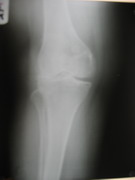

Knee Joint Replacement